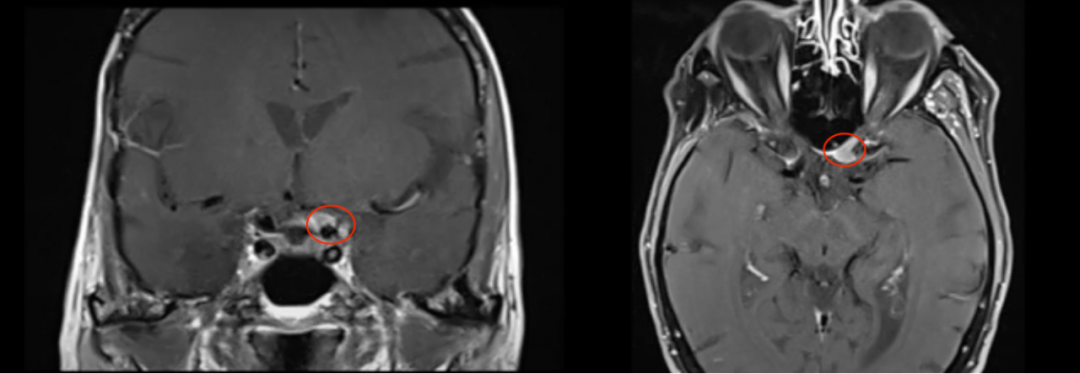

86岁的法国女士Irene(艾琳)就是其中一员,但是她却更加警觉。因为早在2006年,艾琳就因右侧海绵窦区脑膜瘤进行了一次开颅手术。所以当时隔多年后出现视力严重下降的情况,她也并没有以为是年事已高所致,而是警觉来到医院进行核磁检查,而此次就医检查发现左侧视力出现进行性下降,检查视力结果为左侧视力4.6(右侧5.0),左侧视神经管内侧病变均匀增强。检查报告还显示翼点空化是由颞肌萎缩引起的。果不其然,艾琳的视力严重恶化是由于视神经管脑膜瘤导致的。

术前MRI

图5:术前及术后磁共振成像。术前preop(A)和术后Postop(C)显示肿瘤完全切除,视神经保留完好,无脑水肿、出血等。